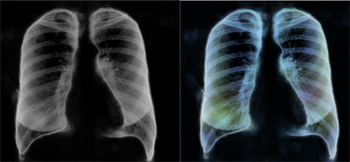

Chest X-ray images which have been pre-processed so an AI algorithm finds them easier to analyse.

For example, it may learn the font the hospital uses to label X-ray images with patients' names, and decide that whenever an image has that font in its labelling, the corresponding patient has COVID-19. One way of getting around this problem is to pre-process X-ray images so that potentially confounding patterns are removed. The AIX-COVNET team have been exploring viable techniques for doing this.